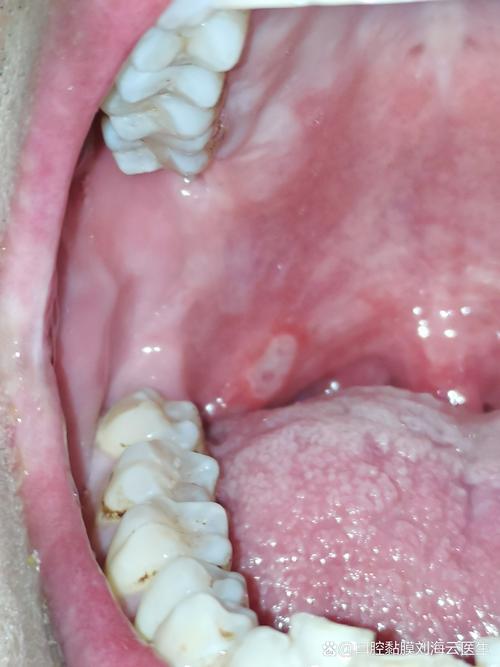

中度口腔溃疡图片示例

以下图片展示了典型中度(重型)口腔溃疡的特征,请注意观察其尺寸、深度和周围组织的炎症反应。

图片1:重型口腔溃疡(舌部)

这张图片清晰地展示了一个位于舌头上的大型、深在性溃疡,它尺寸很大,边缘不规则,中央有黄色假膜,周围红肿范围广,符合重型口腔溃疡的特征。